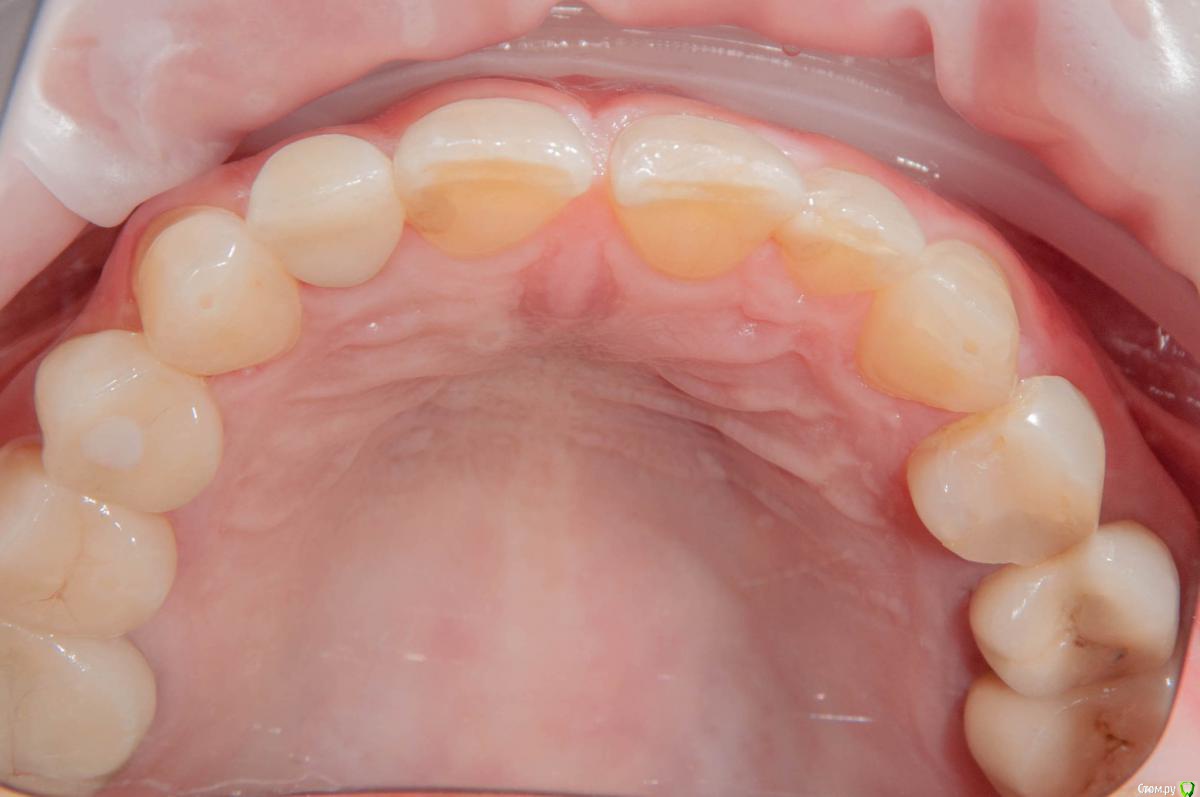

kamranchick Опубликовано 15 ноября, 2018 Поделиться Опубликовано 15 ноября, 2018 Без ССТ, Без Графта. торк 15, нагрузка в течении 8 часов.по последним моим наблюдениям, самое важно это 3д позиционирование имлпнатта, при правильном позиционировании, можно без всех штучек получить приемлимый долгосрочный результат. 5 Ссылка на комментарий

kamranchick Опубликовано 15 ноября, 2018 Автор Поделиться Опубликовано 15 ноября, 2018 Красиво .опишите условия при имплантации - одномоментно сразу после удаления зуба , отсрочено, возраст пациента ...?отлом зуба под десну, одномоментно сразу, женщина, 55 лет 1 Ссылка на комментарий

kamranchick Опубликовано 15 ноября, 2018 Автор Поделиться Опубликовано 15 ноября, 2018 Яйки как у всех)Пациентка мне очень импонировала если честно.Ну и преподаватель в вузе)Ну и двойка, не центральный резец))Тоже были фейлы, теперь минимум на 25 ставим временную коронку 3 Ссылка на комментарий